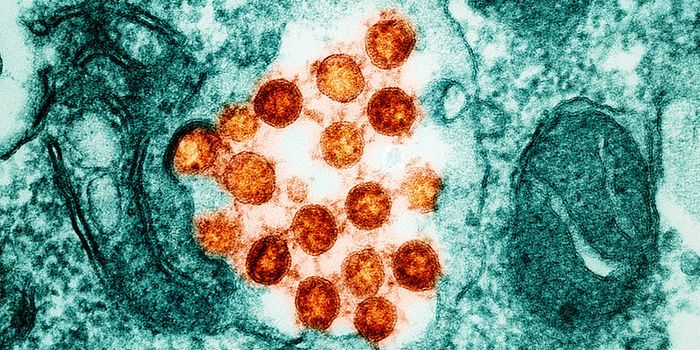

AUG 03, 2022Clinical & Molecular DXWith the 2020 Covid lockdowns still fresh in our minds, the recent outbreak of monkeypox in the United States has many p ...